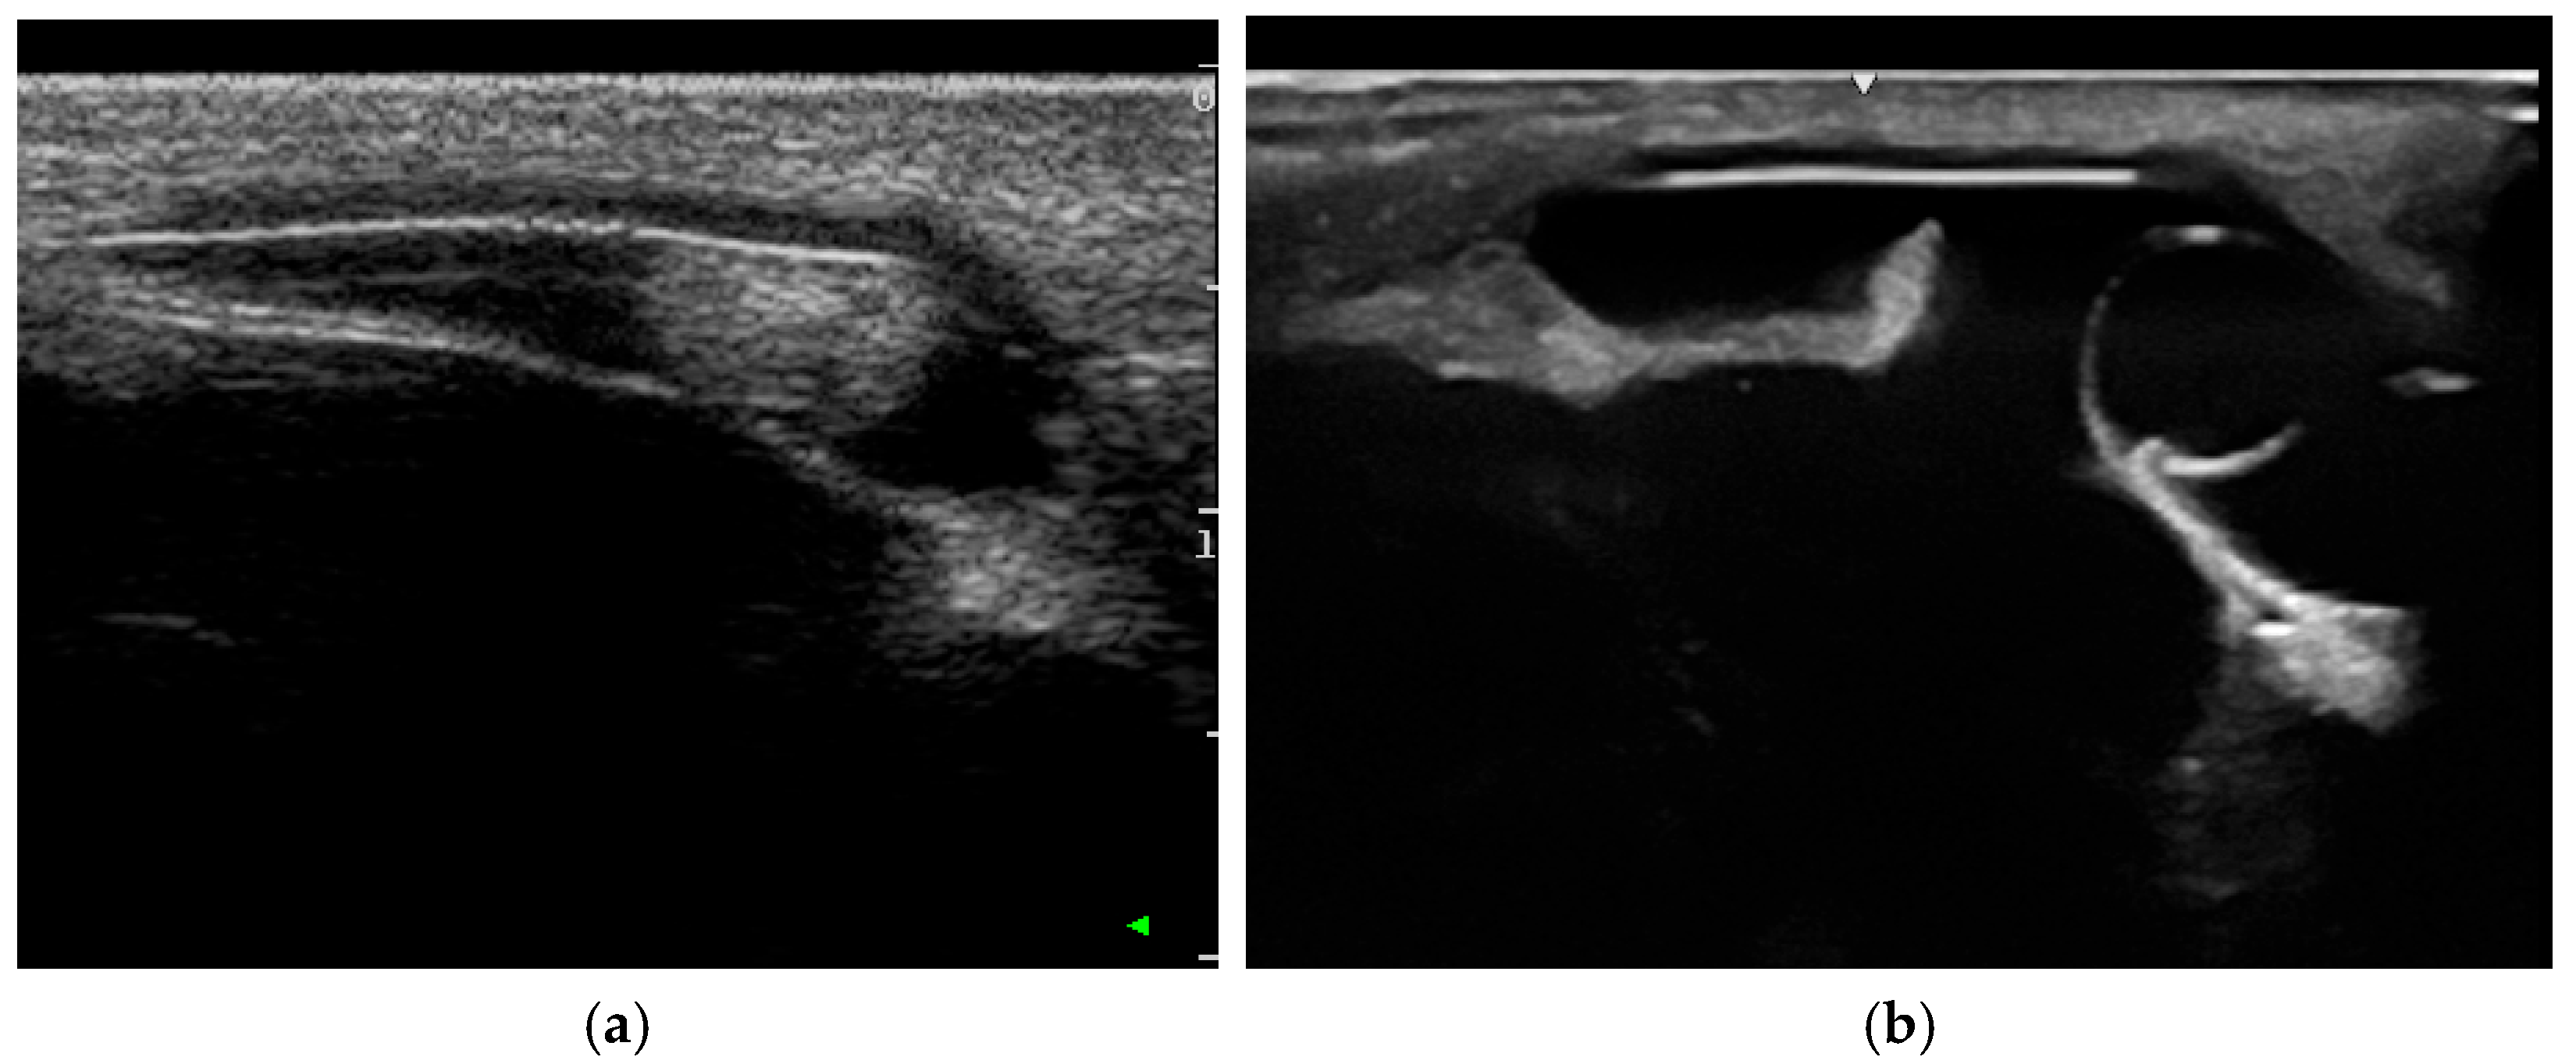

3.2.1. Ultrasonography